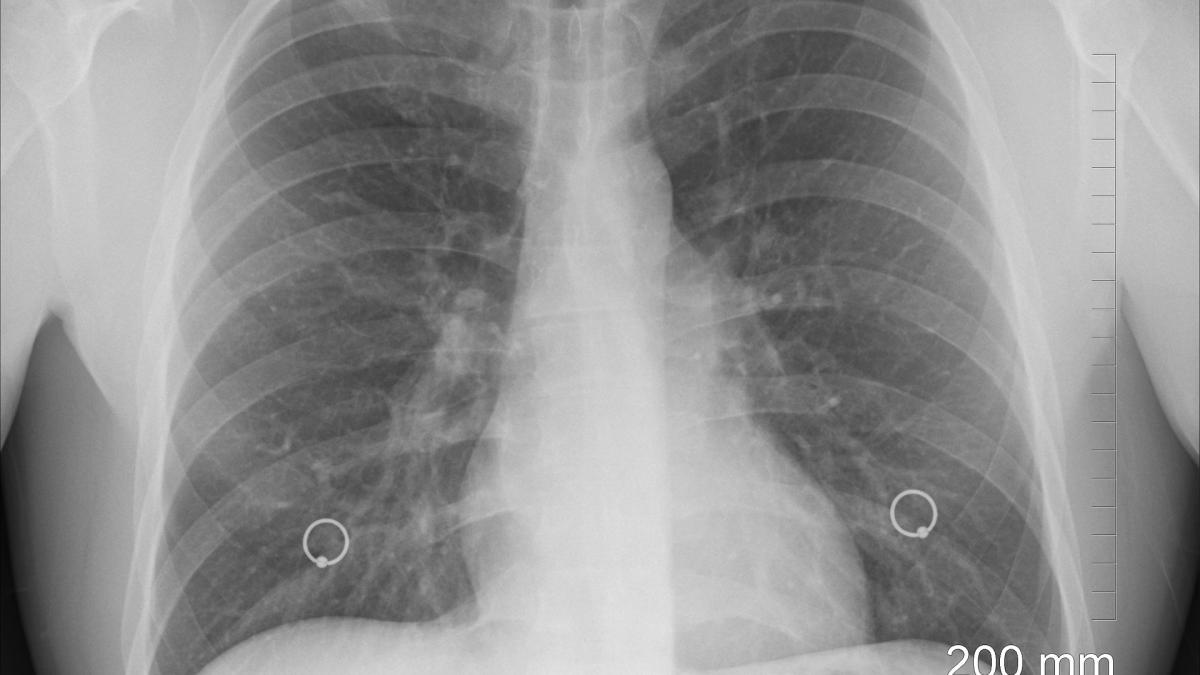

Medicii de la Spitalul Clinic de Boli Infecțioase și Tropicale “Victor Babeș” din București au transmis patru tomografii ale unor pacienți bolnavi de COVID-19, dar nevaccinați. Imagini cu puternic impact.

Tomografiile computerizate cu reconstrucție tridimensională a patru pacienți nevaccinați, bolnavi de COVID-19, recent internați în Spitalul Clinic de Boli Infecțioase și Tropicale “Victor Babeș” din București.